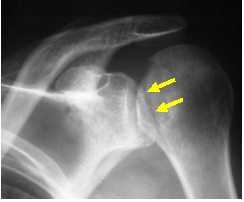

Trough Sign

Impaction of anteromedial aspect of

humeral head